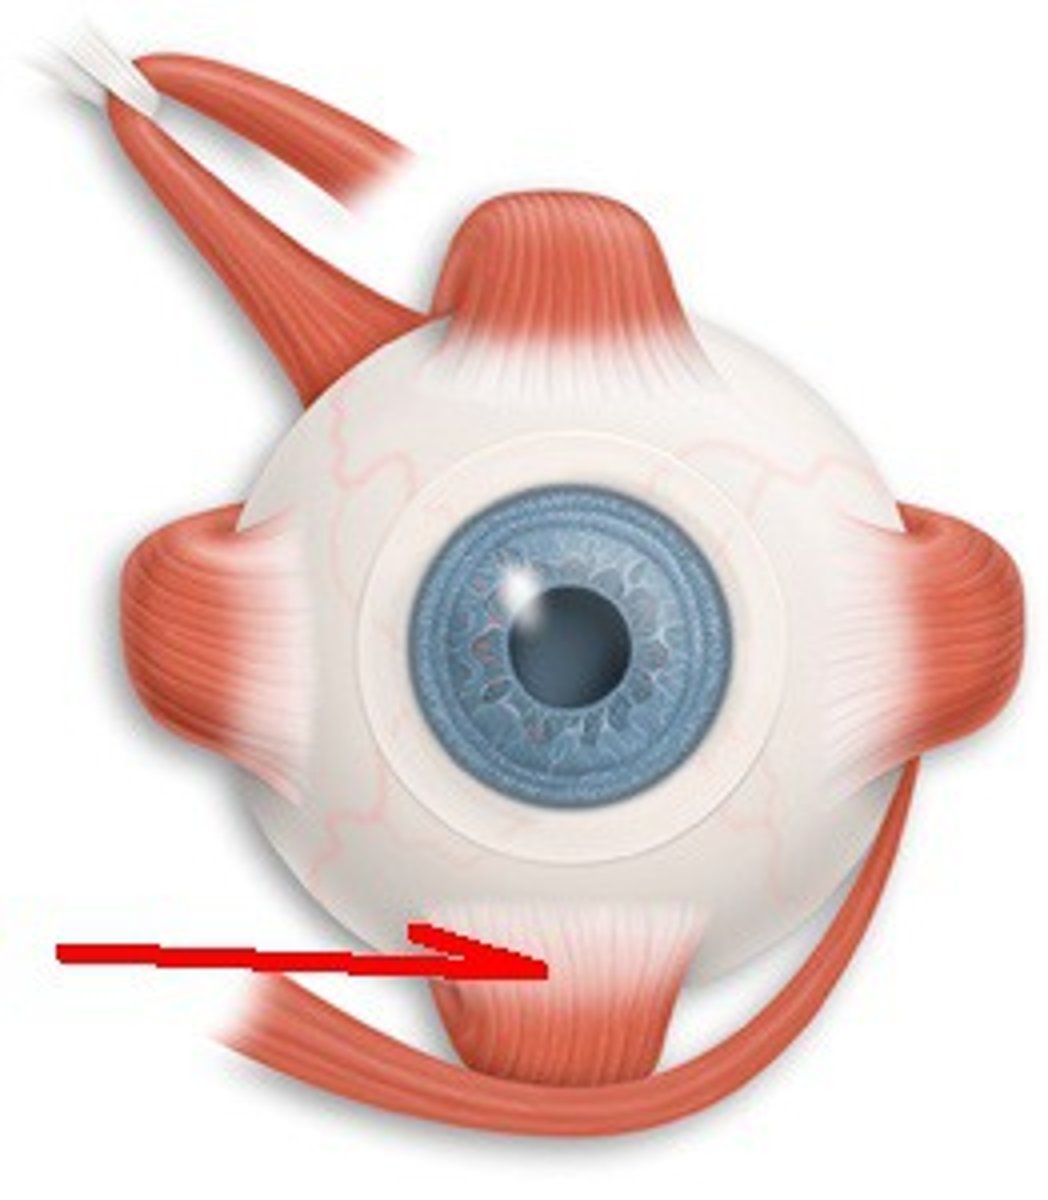

Superior Oblique

A muscle originating in the upper, medial side of the orbit which abducts, depresses and internally rotates the eye

Inferior Oblique

An extraocular muscle, and is attached to the maxillary bone (origin) and the posterior, inferior, lateral surface of the eye

Superior Rectus

One of the extraocular muscles. It elevates, adducts, and helps intort (rotate medially) the eye.

Inferior Rectus

An extraocular muscle. Depresses eye and turns it medially.

Lateral Rectus

A muscle on the lateral side of the eyeball in the orbit

Medial Rectus

The largest of the eye's extraocular movement muscles; adducts the eyeball